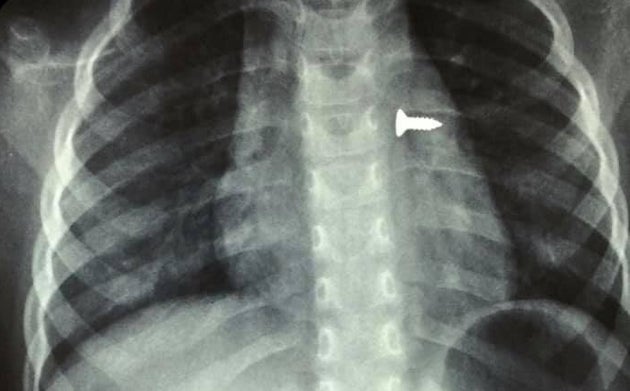

Φωτογραφίες από περιστατικό αφαίρεσης βίδας από το αριστερό βρογχικό δέντρο τρίχρονου κοριτσιού ανέβασε στο Facebook ο αναπληρωτής καθηγητής ΩΡΛ της Ιατρικής Σχολής Κρήτης και Διευθυντής της Ωτορινολαρυγγολογικής Κλινικής του Πανεπιστημιακού Νοσοκομείου Ηρακλείου, Μανώλης Προκοπάκης.

Όπως έγραψε σχετικά στην ανάρτησή του την Τρίτη, «πολύ επείγον χειρουργείο! Πριν από λίγο. Αφαίρεση βίδας από αριστερό βρογχικό δέντρο τρίχρονου κοριτσιού. Πολύ επικίνδυνο... ».